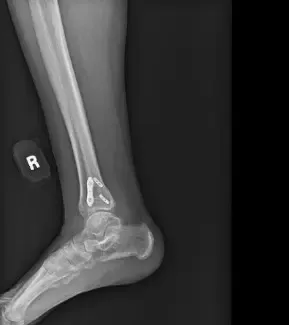

At his four-month follow-up, the patient was fully weight-bearing and had returned to work at full duty. He no longer required a brace and had full ankle stability with minimal pain. Follow-up X-rays showed complete healing with no hardware complications.